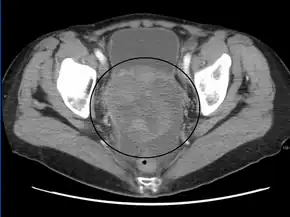

A very large ovarian cancer as seen on CT

Diagnosis of ovarian cancer starts with a physical examination (including a pelvic examination), a blood test (for CA-125 and sometimes other markers), and transvaginal ultrasound.[20] Sometimes a rectovaginal examination is used to help plan a surgery.[23] The diagnosis must be confirmed with surgery to inspect the abdominal cavity, take biopsies (tissue samples for microscopic analysis), and look for cancer cells in the abdominal fluid. This helps to determine if an ovarian mass is benign or malignant.[20]

CT scanning is preferred to assess the extent of the tumor in the abdominopelvic cavity, though magnetic resonance imaging can also be used.[22] CT scanning can also be useful for finding omental caking or differentiating fluid from solid tumor in the abdomen, especially in low malignant potential tumors. However, it may not detect smaller tumors. Sometimes, a chest x-ray is used to detect metastases in the chest or pleural effusion. Another test for metastatic disease, though it is infrequently used, is a barium enema, which can show if the rectosigmoid colon is involved in the disease. Positron emission tomography, bone scans, and paracentesis are of limited use; in fact, paracentesis can cause metastases to form at the needle insertion site and may not provide useful results.[23] However, paracentesis can be used in cases where there is no pelvic mass and ascites is still present.[23] A physician suspecting ovarian cancer may also perform mammography or an endometrial biopsy (in the case of abnormal bleeding) to assess the possibility of breast malignancies and endometrial malignancy, respectively. Vaginal ultrasonography is often the first-line imaging study performed when an adnexal mass is found. Several characteristics of an adnexal mass indicate ovarian malignancy; they usually are solid, irregular, multilocular, and/or large; and they typically have papillary features, central vessels, and/or irregular internal septations.[25] However, SCST has no definitive characteristics on radiographic study.[26]